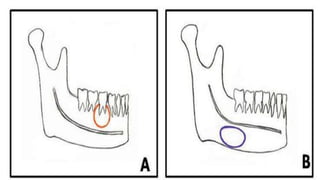

 Benign but locally aggressive odontogenic tumor

 Typical location-posterior mandible (posterior body and ramus).

 Painless swelling/incidental

 Radiolucent, unilocular or multilocular.

 Septations within the lesion -“honeycomb” or “soap bubble” appearance.

 The lesion usually shows marked buccolingual expansion with cortical

thinning/breach . There may be accompanying teeth displacement and resorption.

 Enhancement of solid component on CT and MR.

 Cystic component with low T1W and high T2W signal.

 Diffusion restriction of solid component.

 Pseudocyst

 Angle of jaw

 Aberrant submandibular gland or fat causing remodelling